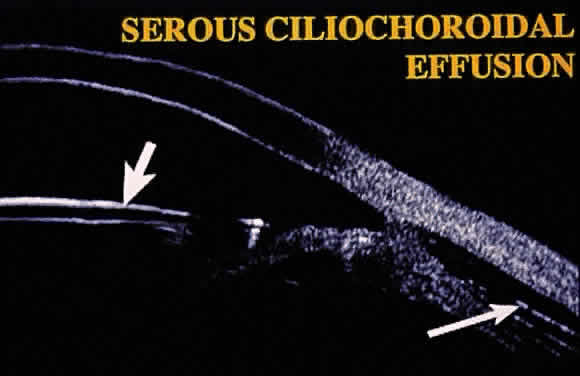

Hypotony (i.e., IOP less than 6 mmHg) after glaucoma surgery can result from excessive aqueous outflow (related to excessive filtration [see later], wound leak, or cyclodialysis cleft) or to reduced aqueous production (related to ciliochoroidal detachment, inflammation, inadvertent use of aqueous suppressants, or extensive cyclodestruction).9 These conditions can coexist. For example, low IOP from overfiltration can induce ciliochoroidal detachment and secondary decreased aqueous production. Possible complications include flat anterior chamber, gradual failure of the bleb, visual loss, cataract, corneal edema, Descemet's membrane folds, choroidal hemorrhage, macular and optic disc edema, and chorioretinal folds (predominantly in young myopic patients). According to Spaeth (Table 1),10 the severity of flat anterior chamber can be classified as grade I when there is peripheral-iris apposition, grade II with pupillary border-corneal apposition, or grade III with lens-corneal touch (see Chapter 15). The central anterior chamber depth also can be described relative to the corneal thickness. Choroidal effusion occurs when fluid collects in the suprachoroidal space (Fig. 2), resulting in forward movement of the lens iris diaphragm with anterior chamber shallowing. On fundus examination, moundlike elevations of the choroid, more commonly in the periphery, are visible.

The initial management of early postoperative hypotony with a formed anterior chamber is conservative. Topical steroids and cycloplegics are used. Restrictions in activity (bending, weight lifting) and avoidance of Valsalva-positive conditions are recommended, especially in patients at risk for suprachoroidal hemorrhage (see earlier). If there is hyposecretion related to intraocular inflammation, ciliochoroidal detachment, or both, the initial treatment consists of intense corticosteroid therapy and long-acting cycloplegics, which stabilize the blood-aqueous barrier. Intervention is indicated in patients with hypotony associated with other complications and in persistent, low IOP with loss of visual acuity and hypotony maculopathy. After filtration surgery, prompt management is indicated, also when there is loss of bleb height. Treatment should be aimed at correcting the specific cause of hypotony. When there is lens-corneal touch (flat anterior chamber, grade III) immediate surgical intervention is necessary to prevent endothelial damage and cataract formation (see Chapter 15). Reformation of the anterior chamber with air, balanced salt solution, or, preferably, a viscoelastic can be done at the slit lamp or under the operating microscope through the paracentesis made intraoperatively. Viscoelastic material is best for maintaining, at least temporarily, the anterior chamber depth. When there are large and appositional choroidal effusions, drainage of the fluid also is necessary (Fig. 4). The technique is described in detail in Chapter 15.